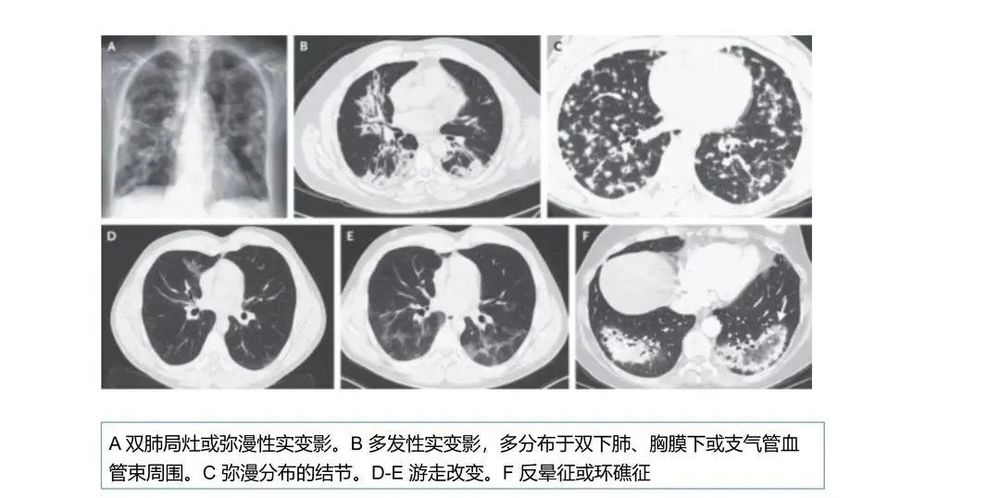

COP肺部CT表现多数为肺泡实变影,可从2cm至双侧广泛病变,病灶多位于胸膜下或肺野外带。病灶呈不规则斑片状,累及多个肺段。部分患者同时可见网状影、不规则线状影和结节影。网格状阴影较少见,很少有胸腔积液等胸膜渗出征象。

①多态性:可呈斑片状、肺实变状、团块状、条索状、地图状、结节状、粟粒状、网织状、蜂窝状等各种形态,以前四种比例较高。每例患者多同时具有两种以上的形态。

②多发性:COP多为两肺多发性病灶。

③多变性:病灶有明显的游走性,具有此起彼伏的特点,多数病例在一周内可见观察到病灶的明显变化。抗感染治疗基本不影响病灶的变化。

⑤多双肺受累:两侧中下肺分布为主,占88%;沿着胸膜分布占96%,不累及胸膜占40%。

通常情况下,提示COP诊断的第一线索来源于其影像学的特点,经过抗感染等治疗效果不佳,结合病理改变,排除其他疾患后诊断为COP。